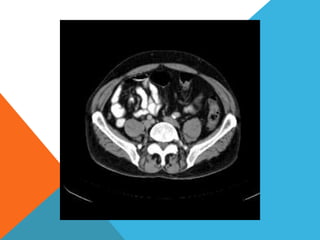

El paciente presentó síntomas de sangrado digestivo y pérdida de peso. Exámenes revelaron gastritis crónica asociada a H. pylori. Un tumor fue descubierto en una colonoscopia normal. La cirugía removió un tumor fibroide solitario, una rara neoplasia mesenquimal que usualmente crece lento y tiene bajo potencial de malignidad. El pronóstico después de la remoción quirúrgica es generalmente bueno.